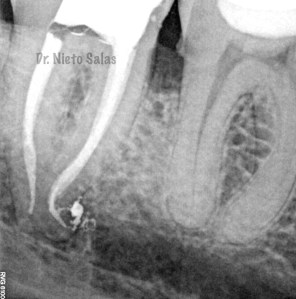

Bueno , ante esta piezas, que presentan una periodontitis apical crónica en la 4.7 y una pulpitis irreversible en la 3.7 nos disponemos a realizar le tratamiento de conductos.

Intentamos mantener la permeabilidad y la forma de  los conductos. Instrumentamos con Pathfile y Mtwo hasta un 25-6%.

Así pues quedaría el sellado hermético y tridimensional:

(buscamos siempre algún conducto lateral, para intentar asegurarnos de su limpieza)